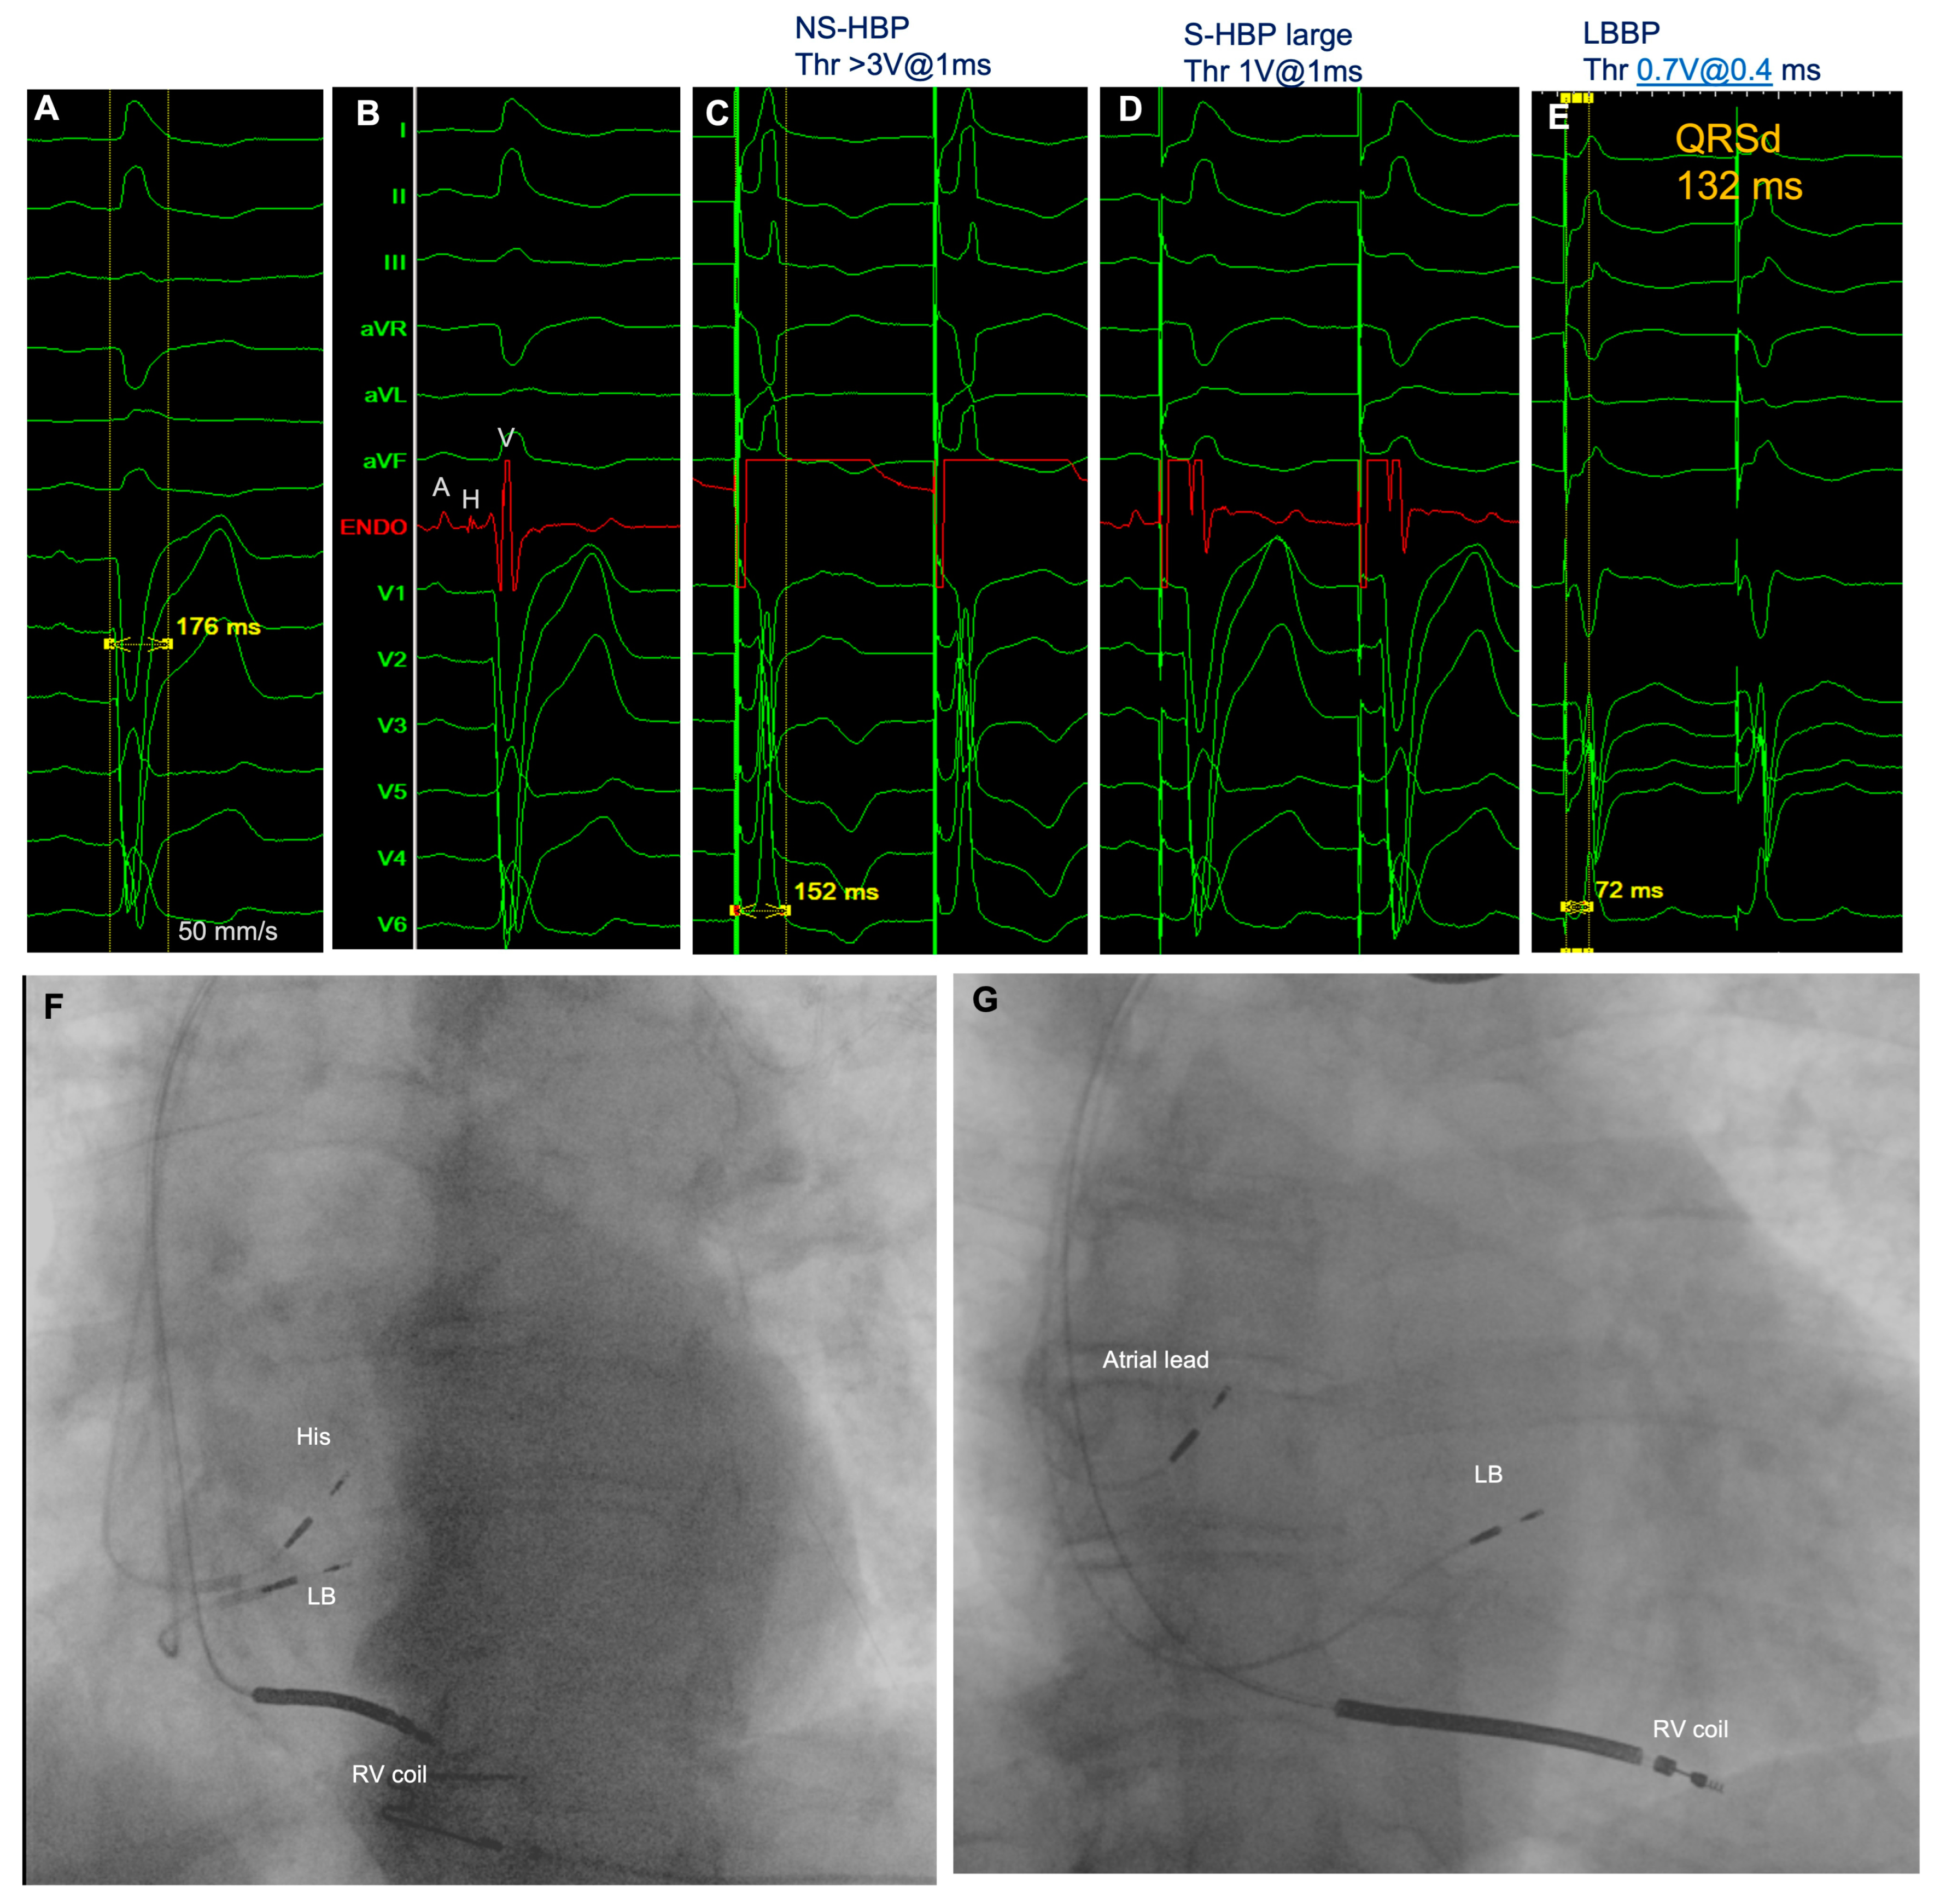

5. CSP to Achieve CRT: Preliminary Experiences

6. Technical Considerations